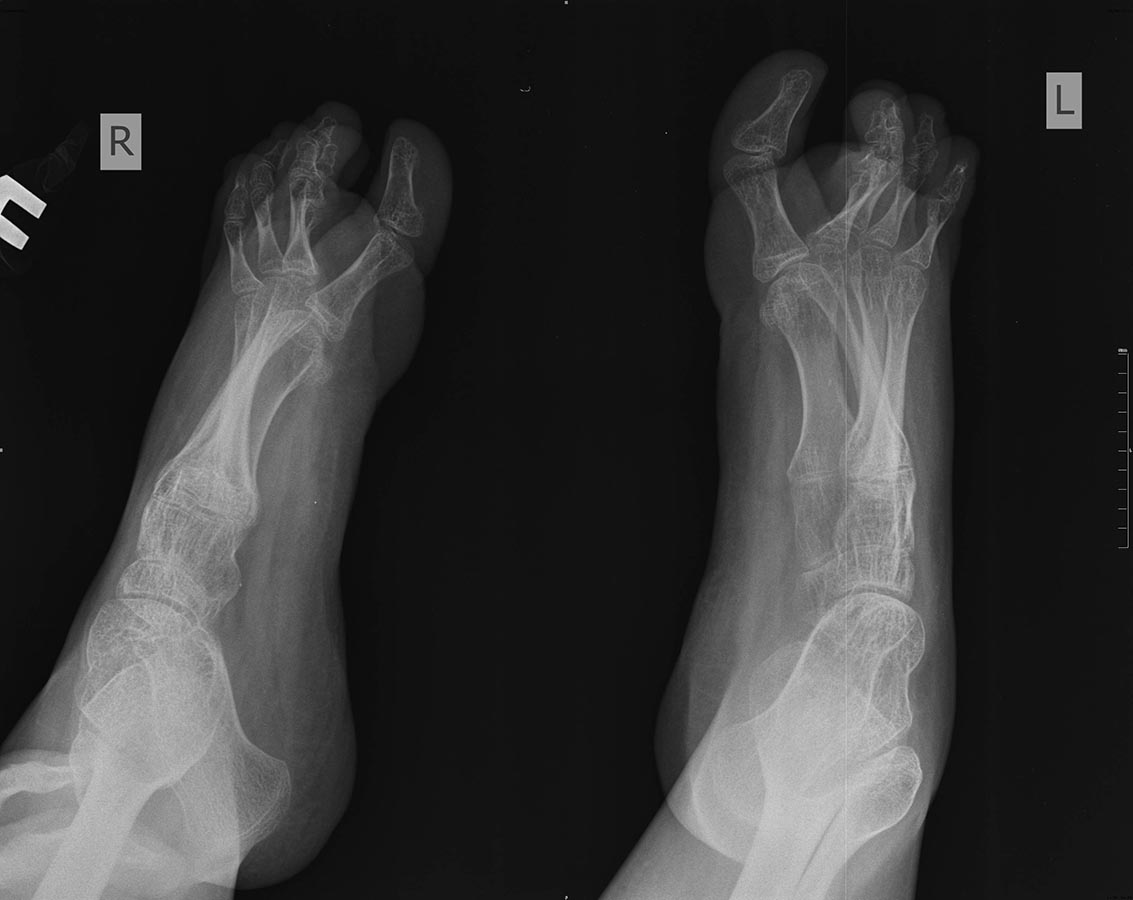

Девочка 15-и лет, страдает ДЦП, квадриплегия, хорошо "разработана", в

8-и летнем возрасте была проведена тенотомия икроножных мышц в

подколенной ямке и приводящих, периодически проходит агрессивную

разработку. До последнего времни могла ходит при помощи палочки, на

ногах AFO. Последний год из-за выраженной эквино-варусной деформации

обеих стоп не может носить ортезы и всвязи с этим ходит при помощи

поддержки матери, стала "колясочной". Учится на отлично! Пассивно стопы

выводятся из эквинуса спокойно, до +5 градусов тыльного

сгибания, в подтаранных суставах пассивные движения отсутствуют,